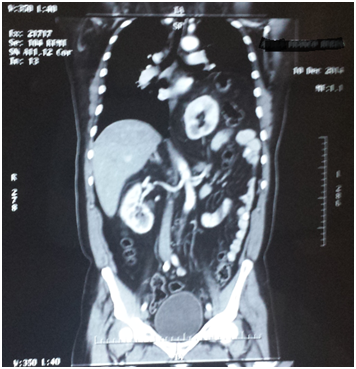

The patient attends the urology outpatient clinic because the previous week he had presented lumbar pain radiating to the right flank as well as the right iliac fossa, intermittent, without fever but with occasional constipation and flatulence. The patient attends to a private’s hospital ER and is prescribed with analgesics, however, 24hours later he presents a new pain condition and attends the same center and undergoes further complete laboratory tests that did not present any alterations. After a throaco abdominal Computerized Axial Tomography with contrast, the presence of intra thoracic ectopic kidney and left diaphragmatic hernia is observed and with a progress caused by the medical treatment administered in the hospital, the patient attends the Urology service due to the presence of left ectopic kidney. Upon arrival to the clinic, the asymptomatic patient does not show any urological pathology and turns out with normal laboratory results (Figure 1-4).

Figure 4 CT sacan show a left kidney near to the heart.